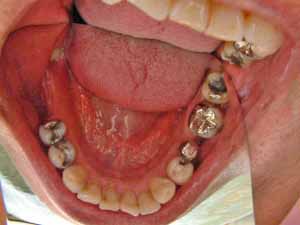

@@R.S‚³‚ñ@56Î —«  ‘åŠw‹³Žö @Žèp“ú@‚Q‚O‚O‚W”N ‚QŒŽ ‚X“úi“yj@㉺Š{  ƒm[ƒxƒ‹ƒKƒCƒhŽg—p@Ö¬“à’ÁÖ@•¹—p@@@

@@@@@ãŠ{  All on ‚U@‘¦Žž‰Ád@@

@@@@@@@@@@@@@ Rpl Tapered Rp  ‚P‚O mm(‚U–{)

@@@@@‰ºŠ{¶‰E@‘¦Žž‰Ád@ ‚R Unit Bridge@

@@@@@@@@@@@ @Rpl Tapered Rp  ‚P‚O mm(‚S–{)@@–ƒWƒ‹ƒRƒjƒAƒNƒ‰ƒEƒ“‚ÅÅI•â’Ô